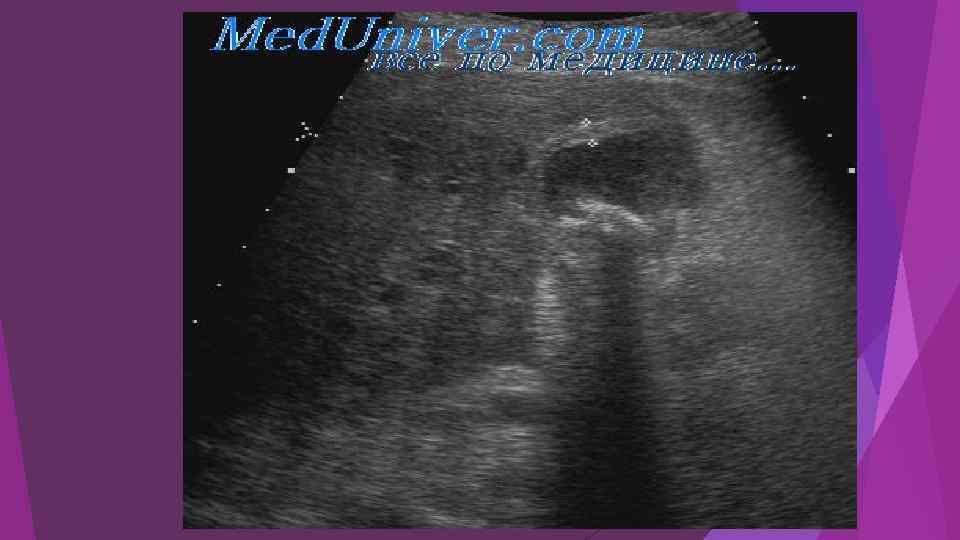

Диагностика острого панкреатита Верификация диагноза должна быть проведена в течение 1 - 2 суток с момента госпитализации. активность панкреатических ферментов в крови (амилаза, липаза), моче (диастаза), перитонеальном экссудате. динамика показателей гомеостаза (лейкоциты крови, гематокрит, глюкоза, билирубин, мочевина, креатинин, общий белок, альбумин, АЛТ, АСТ, ЩФ, ЛДГ, Na, К, Са, Сl, газы крови) комплексное инструментальное обследование: УЗИ забрюшинного пространства и брюшной полости, ФГДС, компьютерную томографию с контрастированием 2 или 3 зон, диагностическую лапароскопию. По показаниям выполняется ЭРХПГ+ ЭПСТ (камень БДС)

Диагностика острого панкреатита Верификация диагноза должна быть проведена в течение 1 - 2 суток с момента госпитализации. активность панкреатических ферментов в крови (амилаза, липаза), моче (диастаза), перитонеальном экссудате. динамика показателей гомеостаза (лейкоциты крови, гематокрит, глюкоза, билирубин, мочевина, креатинин, общий белок, альбумин, АЛТ, АСТ, ЩФ, ЛДГ, Na, К, Са, Сl, газы крови) комплексное инструментальное обследование: УЗИ забрюшинного пространства и брюшной полости, ФГДС, компьютерную томографию с контрастированием 2 или 3 зон, диагностическую лапароскопию. По показаниям выполняется ЭРХПГ+ ЭПСТ (камень БДС)

Острый панкреатит, деструктивная форма. Увеличение размеров

Острый панкреатит, деструктивная форма. Увеличение размеров